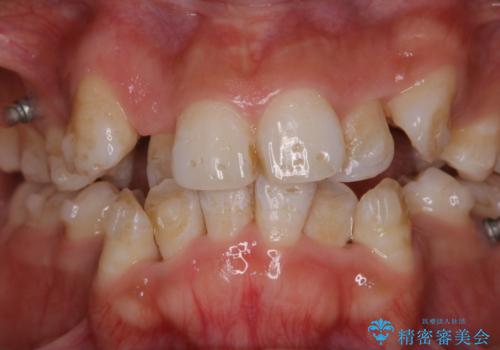

- インビザライン中に、コーヒーによる着色が気になるとのことでした。PMTC60分コースを行いました。

PMTC(保険外治療)は、毎日の歯磨きで落としきれない汚れや、コーヒ、紅茶・タバコのヤニなどの着色も除去します。目には見えない歯と歯の間・歯肉の境目・インビザライン中はアタッチメント周囲などに残っているプラーク(歯垢)もしっかり取り除きます。PMTCでは専門的な機械や材料を使用して、徹底的に汚れを除去するため、虫歯・歯周病・口臭予防などにつながります。